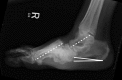

The diabetic Charcot foot syndrome is a serious and potentially limb-threatening lower-extremity complication of diabetes. First described in 1883, this enigmatic condition continues to challenge even the most experienced practitioners. Now considered an inflammatory syndrome, the diabetic Charcot foot is characterized by varying degrees of bone and joint disorganization secondary to underlying neuropathy, trauma, and perturbations of bone metabolism. An international task force of experts was convened by the American Diabetes Association and the American Podiatric Medical Association in January 2011 to summarize available evidence on the pathophysiology, natural history, presentations, and treatment recommendations for this entity.